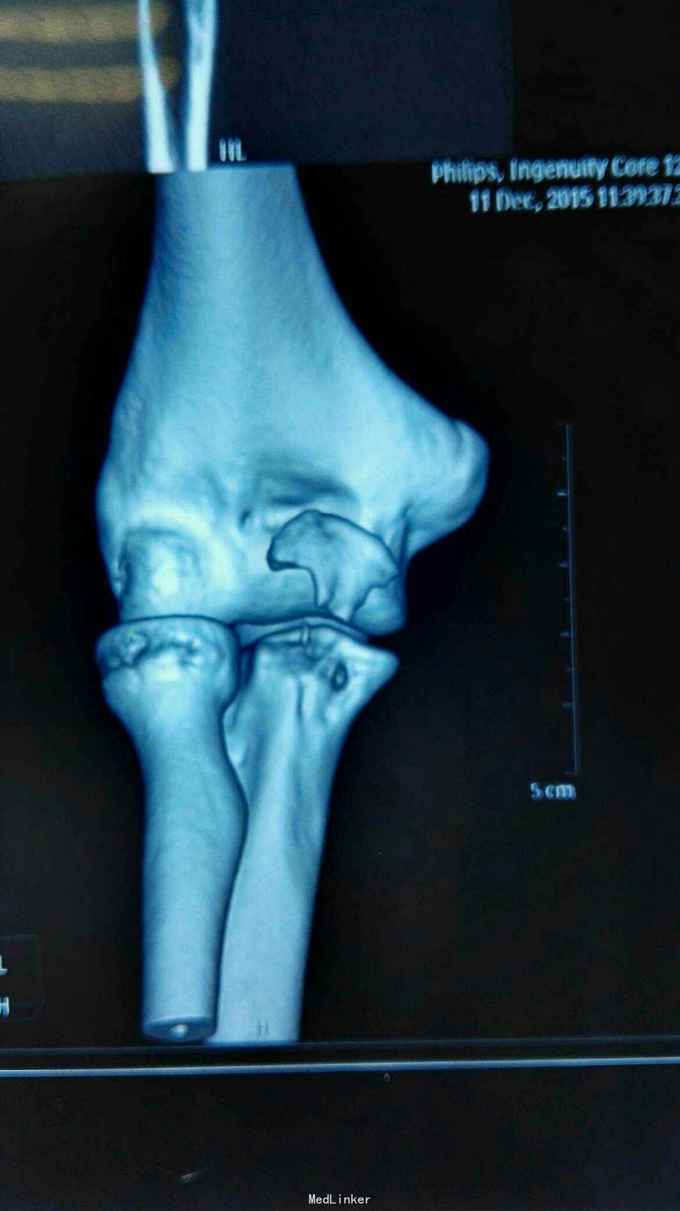

右肘跌伤疼痛伴不能活动1天。 患者,男,14岁,1天前跌倒,感右肘部剧痛,不能活动,急送当地医院拍片示:右肘关节脱位,尺骨冠狀突骨折,右桡骨小头骨折,行手法复位,今来我院就诊。

查体:右肘关节高度肿胀,触痛,活动功能障碍手指末端感觉血运正常。 辅查:x线,CT:右肘关节脱位,右尺骨冠突骨折,右桡骨小头骨折

诊断:右肘恐怖三联症。 治疗:伤后第6天在全麻下行右肘恐怖三联症切开复位内固定术,术中先取肘外侧弧形切口,显露桡骨头,用2枚埋头螺钉固定桡骨头,见右肘外侧副韧带尺侧束断裂,用锚钉固定外侧副韧带。取右肘内侧弧形口,显露冠状突,见冠状突骨折块很小,移位较远,复位,2枚螺钉固定,内侧副韧带前束断裂,修补,术后石膏因定。